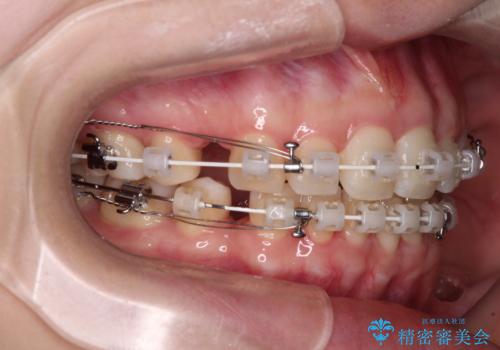

抜歯矯正へ切り替え 表側のワイヤー矯正

- 審美装置

上下前歯が非接触である開咬は、インビザラインによる治療がお勧めではありますが、非抜歯矯正か抜歯矯正か悩む口元であり、途中抜歯矯正に切り替えたときに対応しやすいよう、ワイヤー装置にて治療を行うこととしました。

舌の突出癖の影響もあり、非抜歯矯正で治療開始したものの口元が突出し、唇が閉じにくくなってしまったため、途中で第一小臼歯4本を抜歯ししました。